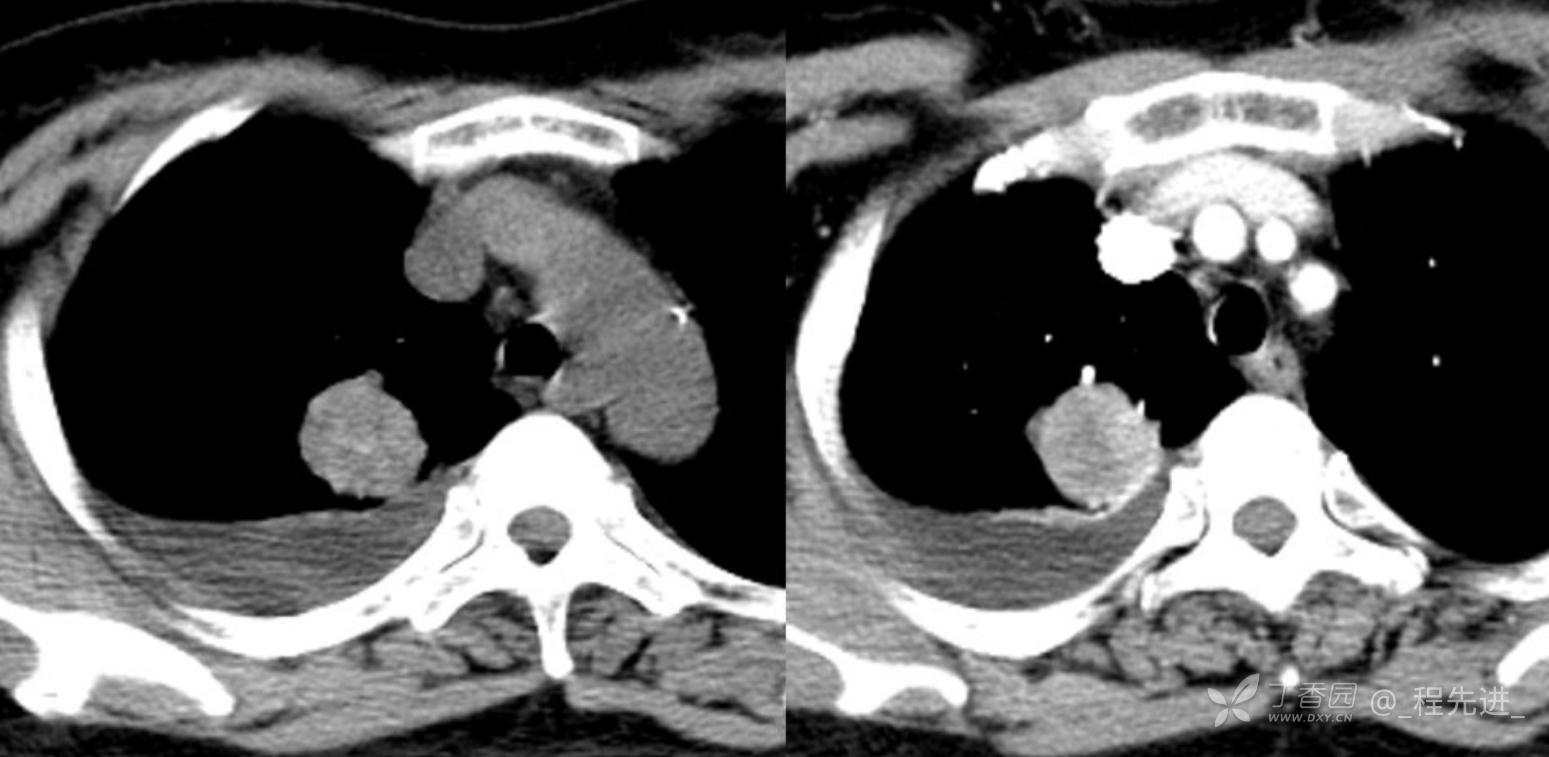

简要病史:乏力、纳差20余天,皮肤巩膜黄染半月偶有咳嗽,咳白痰,全身皮肤巩膜黄染。无咯血,无明显胸闷、胸痛,无明显气促,无发热及盗汗。精神欠佳,纳差,睡眠一般,二便正常